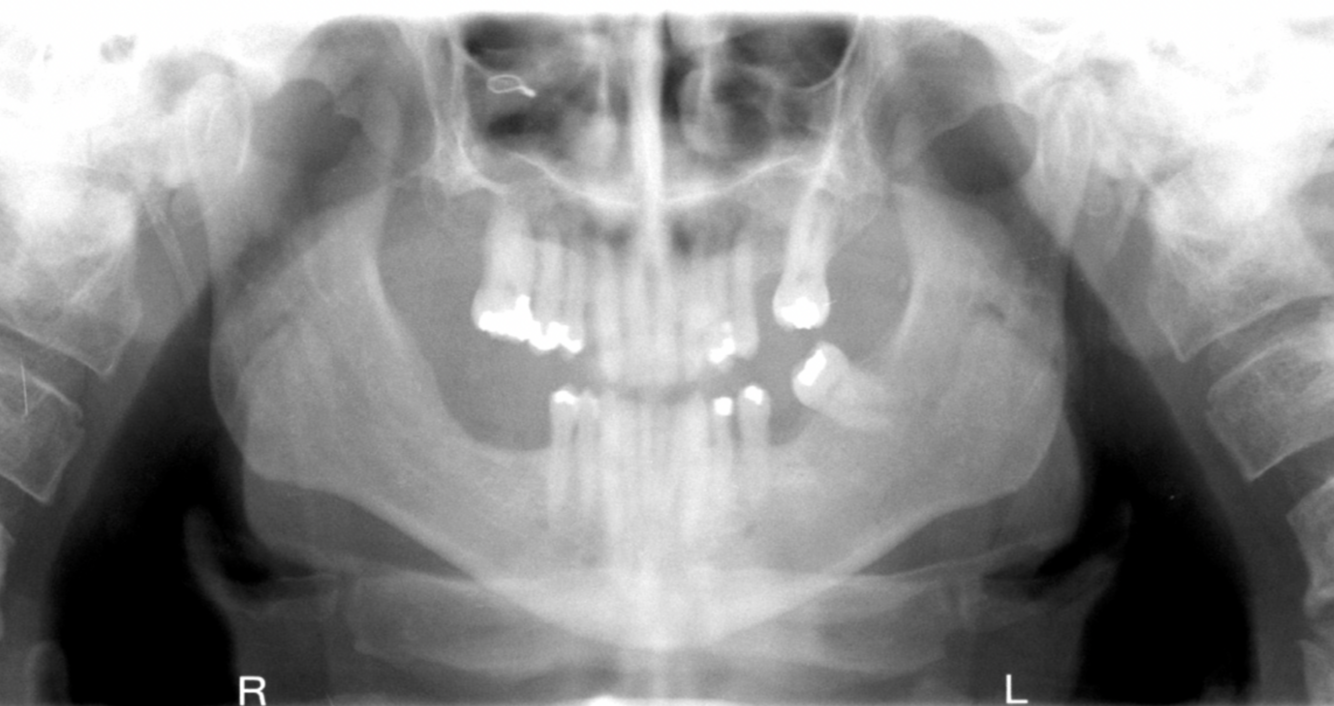

What errors can be seen in the following radiograph, what is the cause?

1. excessive curvature of the occlusal plane 2. roots of mandibular anterior teeth are blurred 3. rami/condyles are tipped inward 4. condyles are close to or cut off top of image 5. hyoid bone superimposed on mandible Cause: chin down